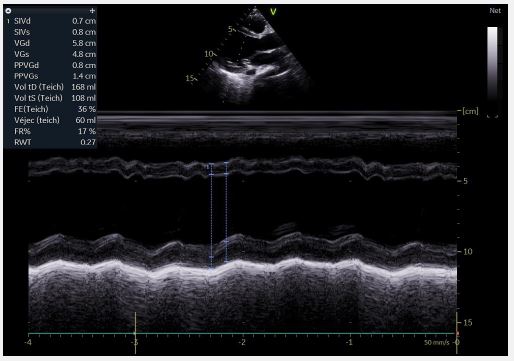

Echocardiography revealed a restrictive PDA with a 6-mm diameter and a significant gradient, along with mobile vegetation attached to the pulmonary valve leaflets and the origin of the pulmonary artery (Figure 1), leading to severe pulmonary insufficiency. The mitral valve was calcified with a vegetation measuring 11×7 mm, and mild mitral regurgitation was noted. The Left Ventricle (LV) was dilated with reduced ejection fraction (Figure 2). The Right Ventricle (RV) was non-dilated with preserved systolic function. The Inferior Vena Cava (IVC) was slightly dilated but compliant. Extension investigations found no septic emboli.

Image is Not Display Check it

Figure 2: Dilated LV with reduced ejection fraction.